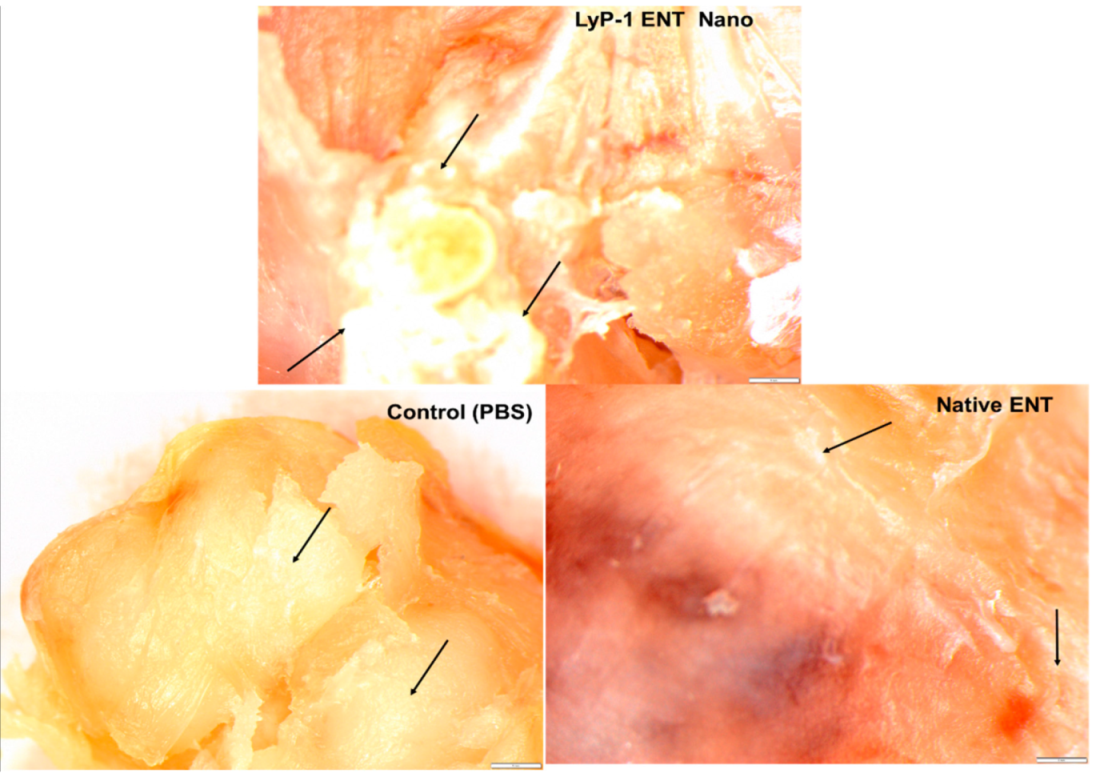

2.7. Tumor Necrosis on KYSE-30 Xenograft